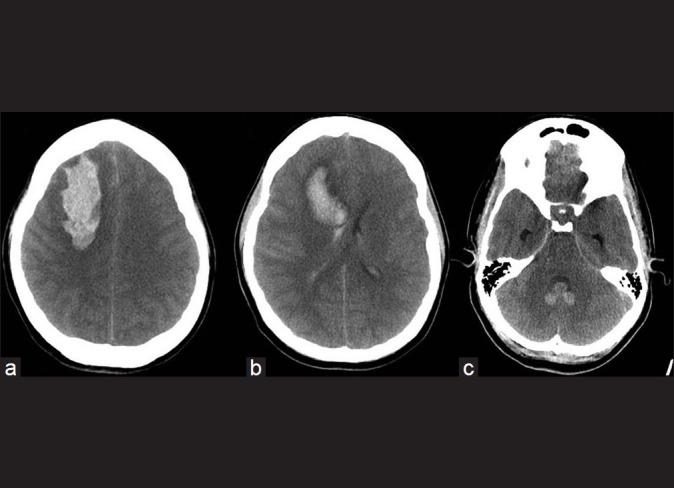

We describe an atypical case of a patient with no risk factors who developed sudden eclampsia and spontaneous intracerebral hemorrhage during the 34(th) week of pregnancy. She underwent successful emergent Cesarean section followed by craniotomy. Both intraoperative surveillance and postoperative magnetic resonance angiographic examination of the cerebral vessels failed to identify an aneurysm, arteriovenous malformation, tumor, or leptomeningeal disease.

我们描述了一例非典型病例,该患者无危险因素,在妊娠第34周时突然发生子痫和自发性脑出血。她成功接受了急诊剖宫产,随后进行了开颅手术。术中对脑血管的监测以及术后的磁共振血管造影检查均未发现动脉瘤、动静脉畸形、肿瘤或软脑膜疾病。